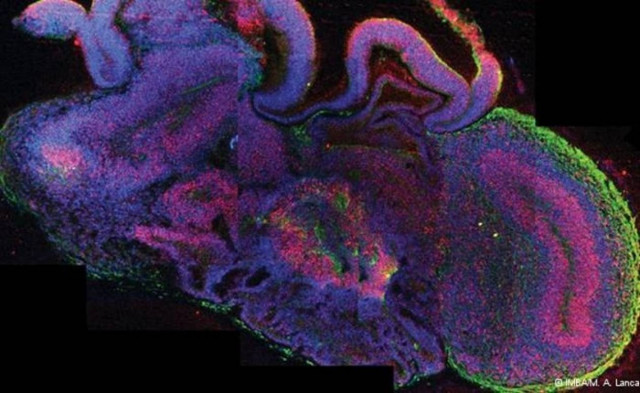

Μικροσκοπικούς εγκεφάλους μεγέθους 4 χιλιοστών κατάφεραν να αναπτύξουν στο εργαστήριο ο επιστήμονας Γιούργκεν Κνόμπλιχ και οι συνεργάτες του από το Ινστιτούτο Μοριακής Βιοτεχνολογίας της Βιέννης.